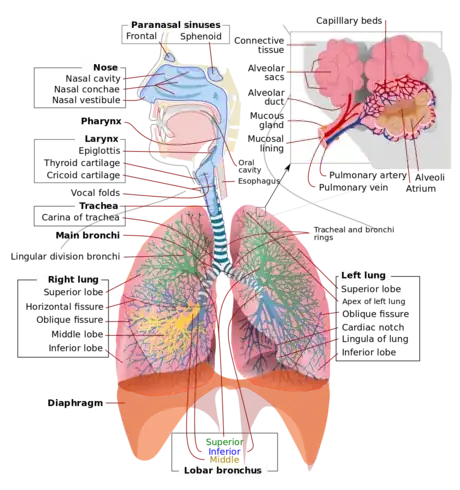

This guide will provide a description and example of how to draw the human respiratory system. First by outlining the lungs, bronchi, and trachea, then detailing additional components and accessory structures. By the end of this wikiHow, you will be proficient in drawing a medically accurate human respiratory system and be ready to ace your exams!

1Select a dynamic color scheme. For this activity, you will need 1-2 low contrast colors and 9 highlighting colors. There are several medical illustration standards to keep in mind, such as using blue for oxygenated blood flow and red for deoxygenated blood flow. Beyond those standards, it’s up to you how detailed you need your illustration to be.

2Select a reference photo. Choose a reference photo online or from your textbook to follow along with.Advertisement

3Detail the lobes of the lungs. Segment the right lung into 3 curved sections (draw the oblique and horizontal fissures) and the left lung into 2 curved sections (draw the oblique fissure) as distributed below; these segments are called lobes.

4Outline the branching. Extend the branching of the bronchus in each lung into a secondary bronchus in each lobe. Then extend this secondary branching with smaller bronchioles. It is helpful to do each lobe branch in a new color to distinguish the branching pattern.

5Draw a microscope bubble. Attached to these bronchioles are alveoli, which appear as small grapes. Detail several of these and then extend a microscope box away from your diagram to illustrate this structure more clearly.

6Detail the alveoli. Redraw a segment of the bronchioles and attached alveoli in the microscope box. The bulbous “grape” like structures of the alveoli are called alveolar sacs, and the segment of branching immediately before the alveoli are called alveolar ducts.

- In addition to these structures, draw an overlay of the pulmonary artery (red) and pulmonary vein (blue) leading into the arteriole and venule capillary system.

7Label your completed diagram. Draw lines away from each structure to an open space using a ruler or straight edge. Clearly label each structure or region correctly. For more complex drawings, it is sometimes beneficial to label structures numerically and then provide an organized key.